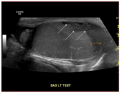

Presumed testicular rupture during a college baseball game: a case report and review of the literature for on-field recognition and management. Freehill MT, Gorbachinsky I, Lavender JD, Davis RL, Mannava S - Sports health (2015)

| current | 17:42, 3 May 2023 | 512 × 395 (122 KB) | Rossdonaldson1 (talk | contribs) | Presumed testicular rupture during a college baseball game: a case report and review of the literature for on-field recognition and management. Freehill MT, Gorbachinsky I, Lavender JD, Davis RL, Mannava S - Sports health (2015) |